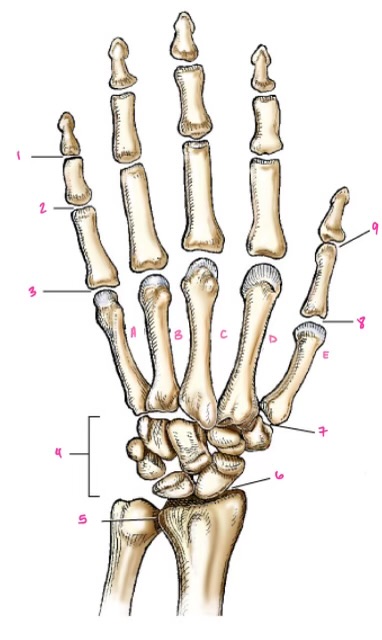

1

1

2

2

3

3

4

9

5

10

6

11

7

14

8

15

9

16

10

17

11

18

1

13

2

14

3

15

4

16

5

17

6

18

7

19

8

20

9

7

22

8

23

9

24

10

25

11

26

13

27

14

28

15

29

16

30

17